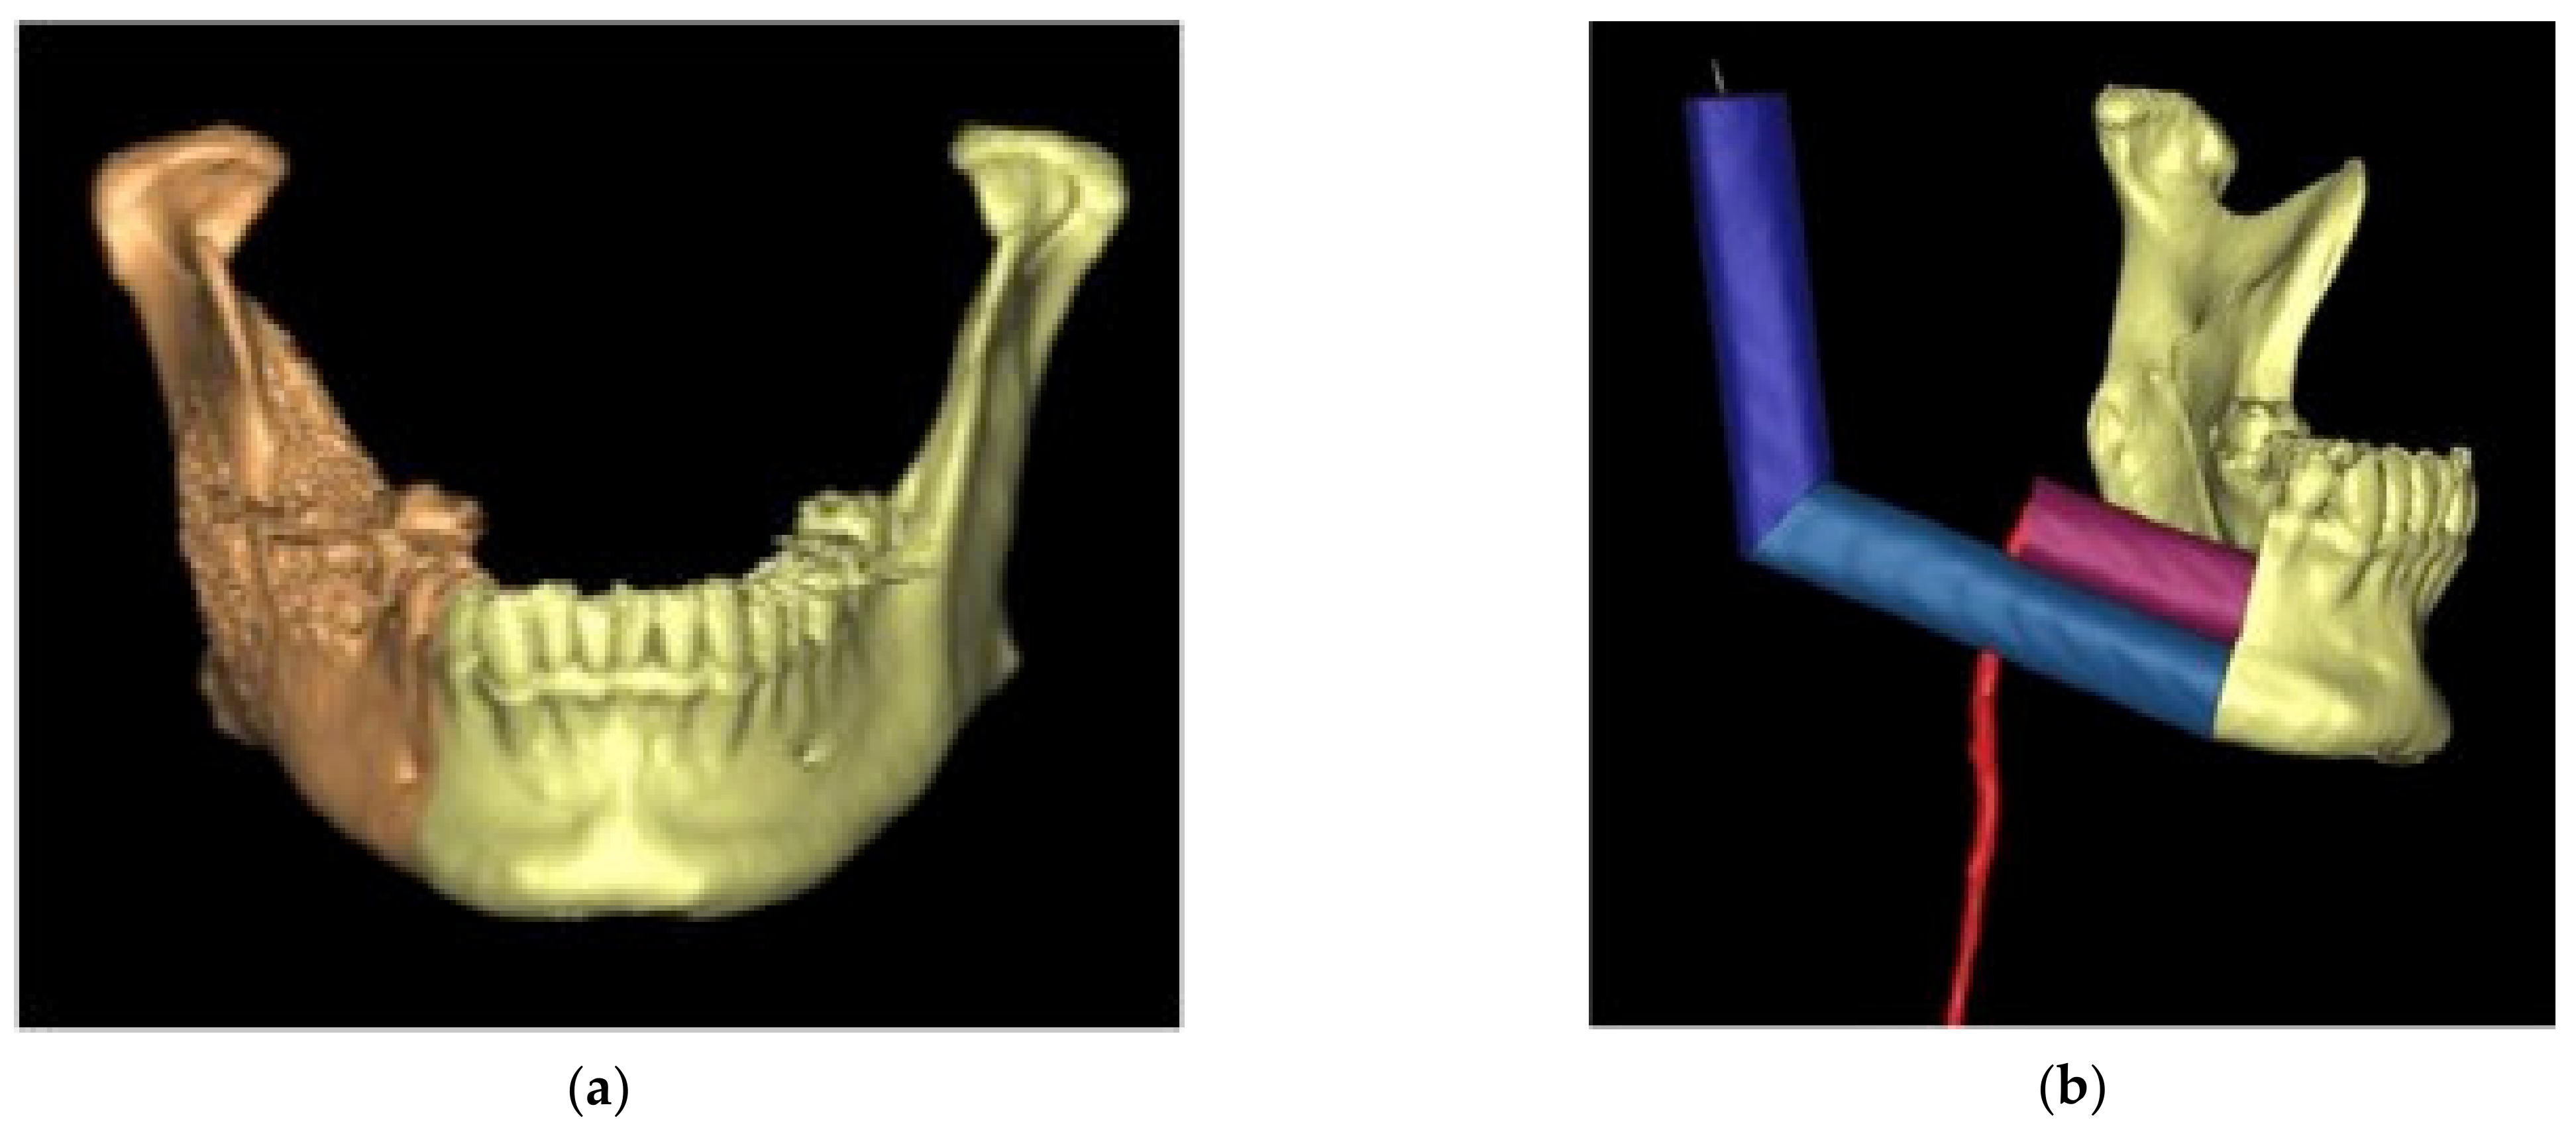

2.2. Virtual Planning

2.5. Intra-Operative Surgical Navigation

2.6. Post-Operative Evaluation